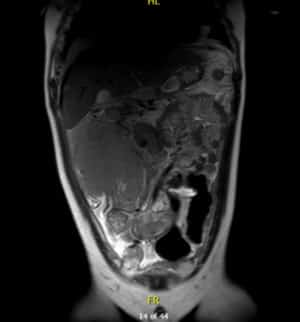

Resonancia magnética

Por su parte, en la resonancia magnética se observa una masa voluminosa infiltrativa en flanco derecho que mide 140 x 120 x150 mm, íntima relación con área ileocecal y colon ascendente al que rodea en su totalidad sin condicionar obstrucción.